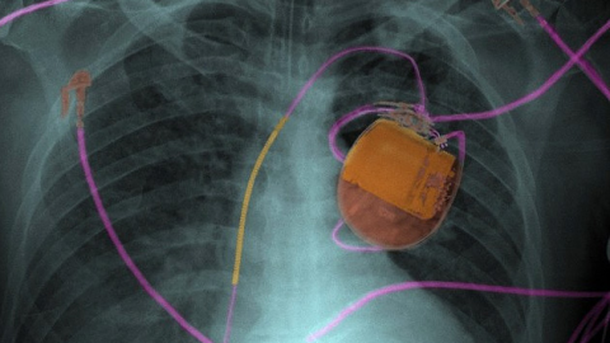

El tema es que en el futuro, y se puede ver esa tendencia en la actualidad, la tecnología estará más y más conectada a Internet y los criminales aprovecharán para realizar asesinatos. Un claro ejemplo es un marcapasos que se maneje de forma remota. Como podría suceder en una película de ciencia ficción, un hacker podría acceder al mismo y desactivarlo. Lo mismo con un automóvil, o un sistema de terapia intensiva.

Si bien no se sabe lo que sucederá en el futuro, la realidad es que en la actualidad, si bien no se usan de manera masiva, ya existen implantes que tienen conectividad y que pueden ser controlados por médicos de forma remota.